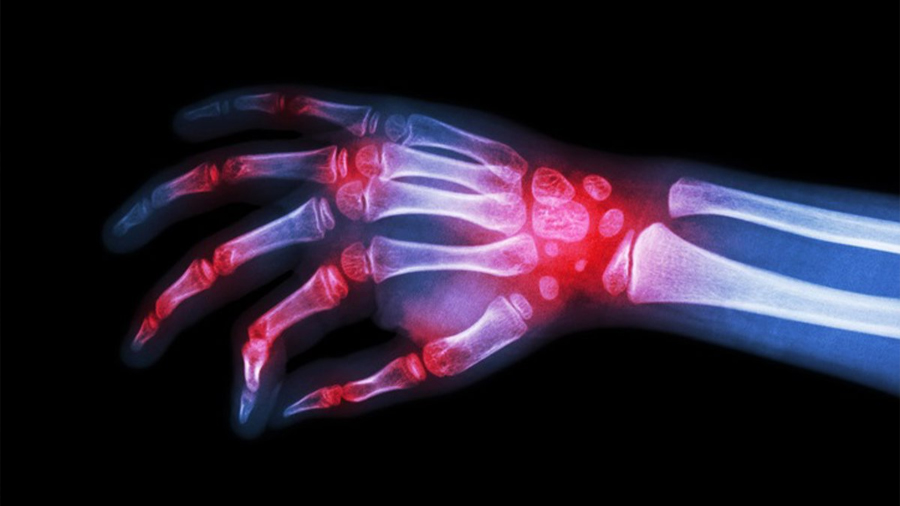

Mientras que la artrosis se relaciona con el desgaste progresivo del cartílago articular, la artritis implica un componente inflamatorio más marcado que puede afectar a personas de distintas edades.

«Los cambios de temperatura y de humedad influyen en cómo las articulaciones gestionan la inflamación y en cómo el sistema nervioso interpreta el dolor. En épocas de frío y humedad se observa más rigidez, menor elasticidad de los tejidos y una percepción más intensa de las molestias, especialmente en pacientes con artrosis y artritis. Si a esto se suma una menor actividad física, el resultado suele ser un empeoramiento de los síntomas», ha señalado Terán.